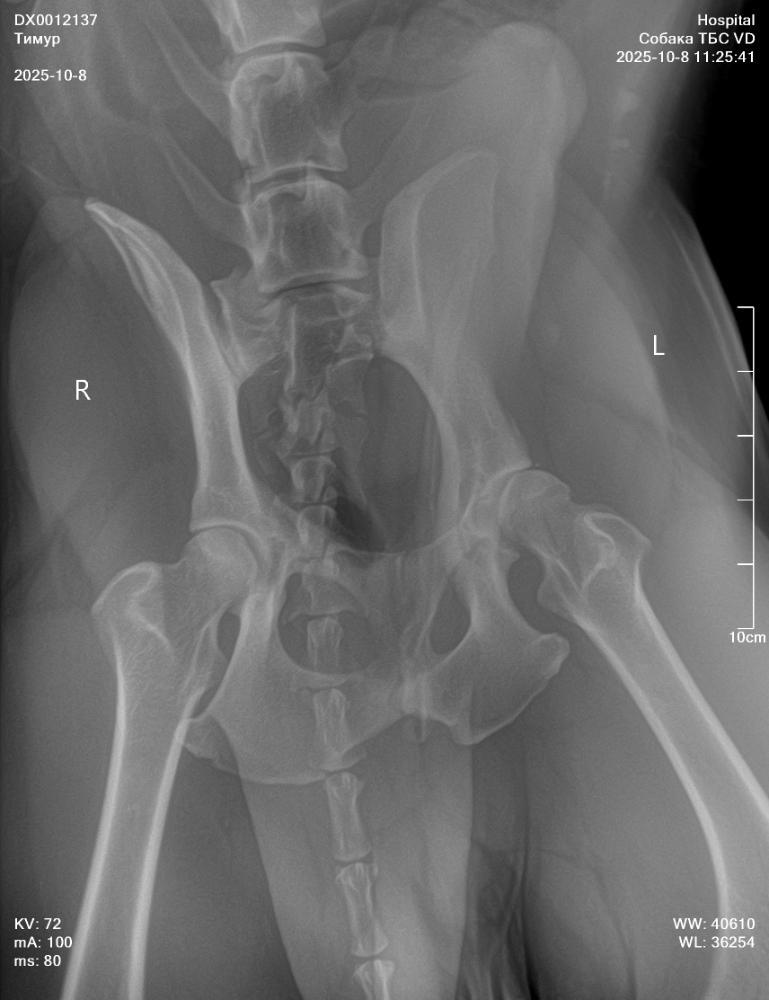

NataP Опубликовано 8 октября, 2025 Опубликовано 8 октября, 2025 Здравствуйте. Три дня назад после прогулки Тимур захромал, хотя сильных нагрузок не даём, немного поиграли с пуллером. Сегодня създили в клинику, сделали снимки без седации, кое как смогли завалить, сопротивлялся, поэтому снимки получились не такие, как хотелось бы. Но даже по ним нам ставят дисплазию и рекомендуют операцию по протезированию. Хочу проконсультироваться онлайн в Москве. Посоветуйте, пожалуйста, где сейчас лучше консультироваться, и подойдут ли такие снимки, или лучше переделать под седацией. Сейчас пока выписали онсиор или робексеру на 10 дней, но Омез сказали, давать не нужно, а я сомневаюсь, может всё-таки давать? Простите за много букв, просто в панике пока, а кроме вас не к кому обратиться. Снимки прикрепила.

Кирюша и Маруся Опубликовано 9 октября, 2025 Опубликовано 9 октября, 2025 Снимки без седации полная дезинформация. А к врачам, которые делают их для постановки диагноза лучше не ходить. Сделайте нормальные снимки с седацией у профи. При сомнении и пон азначению врача - МРТ. А обезбол крупной моложой собаке на травированную связку - это странно, так как нужно граничивать движение, а не просто снимать болевой и давать скакать. По врачам в МСК: Мезин, Еремин, Ягников, Воронцов, Самошкин, Середа, Давыдов, Гранин... Выбирайте любого. Нормальные рентгены делают они все. 1

NataP Опубликовано 9 октября, 2025 Автор Опубликовано 9 октября, 2025 То есть эти снимки вообще безполезны? Зря только с Тимуром воевали, чтоб на стол уложить(

Звезда Севера Опубликовано 9 октября, 2025 Опубликовано 9 октября, 2025 К сожалению, да. Такие снимки не информативны. Я так понимаю, что вам ближе в Нижний Новгород ехать? Может, там найти хороших специалистов?